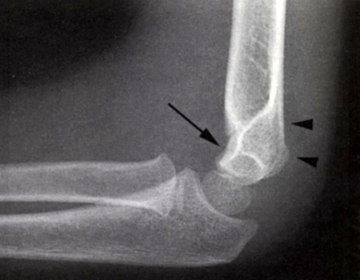

En linie gennem centrum af radius skal altid gå lige igennem capitulum humeri.

En linie langs forsiden af humerus går normalt igennem midterste 1/3 del af capitulum humeri, hvis capitulum ligger bagved skal der reponeres og osteosynteres i GA. Hos børn under 4 år tillades lidt større dislokation.